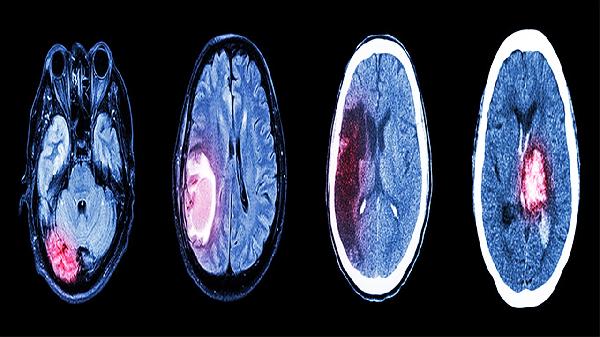

3、改善心脑供血

通过增加冠状动脉和脑动脉血流量,缓解心肌缺血和脑供血不足。对动脉粥样硬化引起的头晕、记忆力减退有一定改善效果。使用期间应注意血压变化,严重心功能不全者需谨慎。

药物成分能抑制血小板活化因子,预防血栓形成。适用于高血脂、高血压患者的二级预防,降低脑梗死复发风险。但手术前需告知医生用药史,避免术中出血并发症。

5、辅助治疗心脑血管疾病